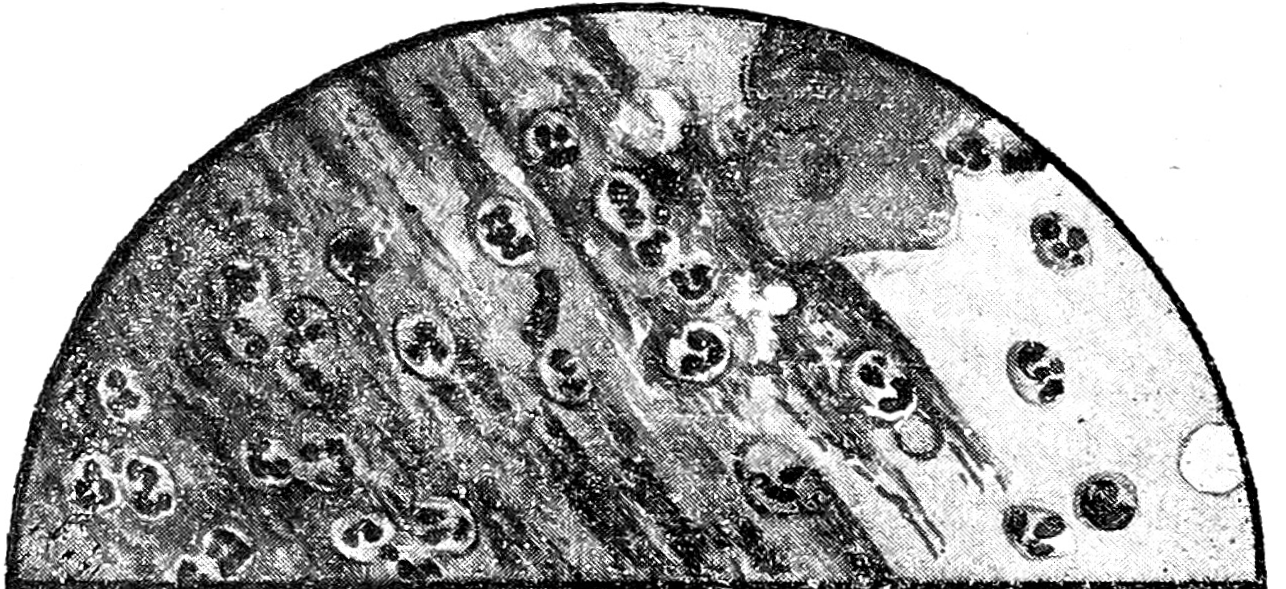

Рис. 1. Vitium cordis и застойные явления в легких. Слизистый фон с пузырьками воздуха, N, много AM.

Общие свойства окраски всех этих клеток, наличность переходов между ними, появление их при заинтересованности альвеол и отсутствие в случаях чистых бронхитов (где паренхима легких не затронута)—все это говорит за то, что перечисленные элементы одного происхождения, находятся в зависимости от состояния альвеол и представляют собою ничто иное, как клетки альвеолярного эпителия, изменившиеся под влиянием раздражения и приобревшие гистиоцитарные свойства.